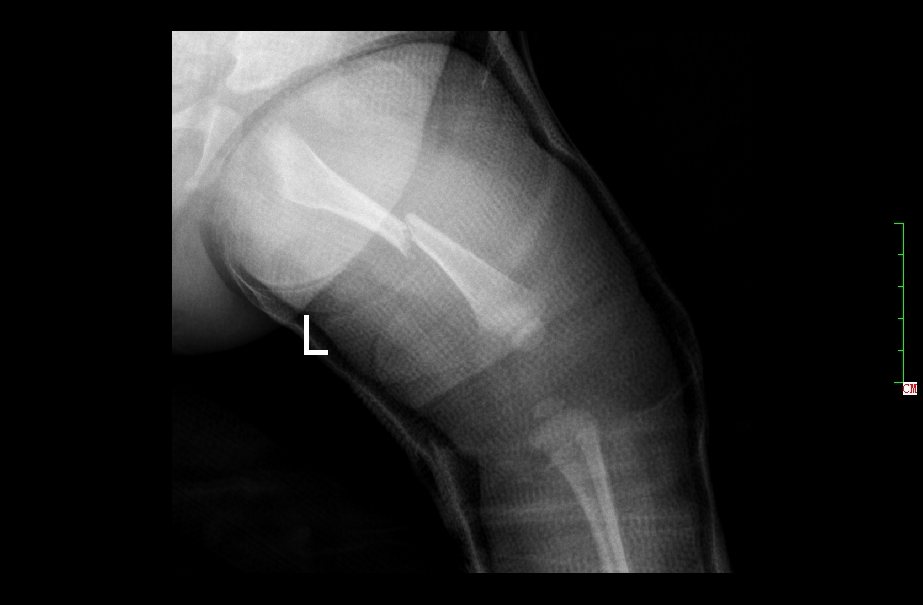

2 月后复查正位片

2月后复查侧位片